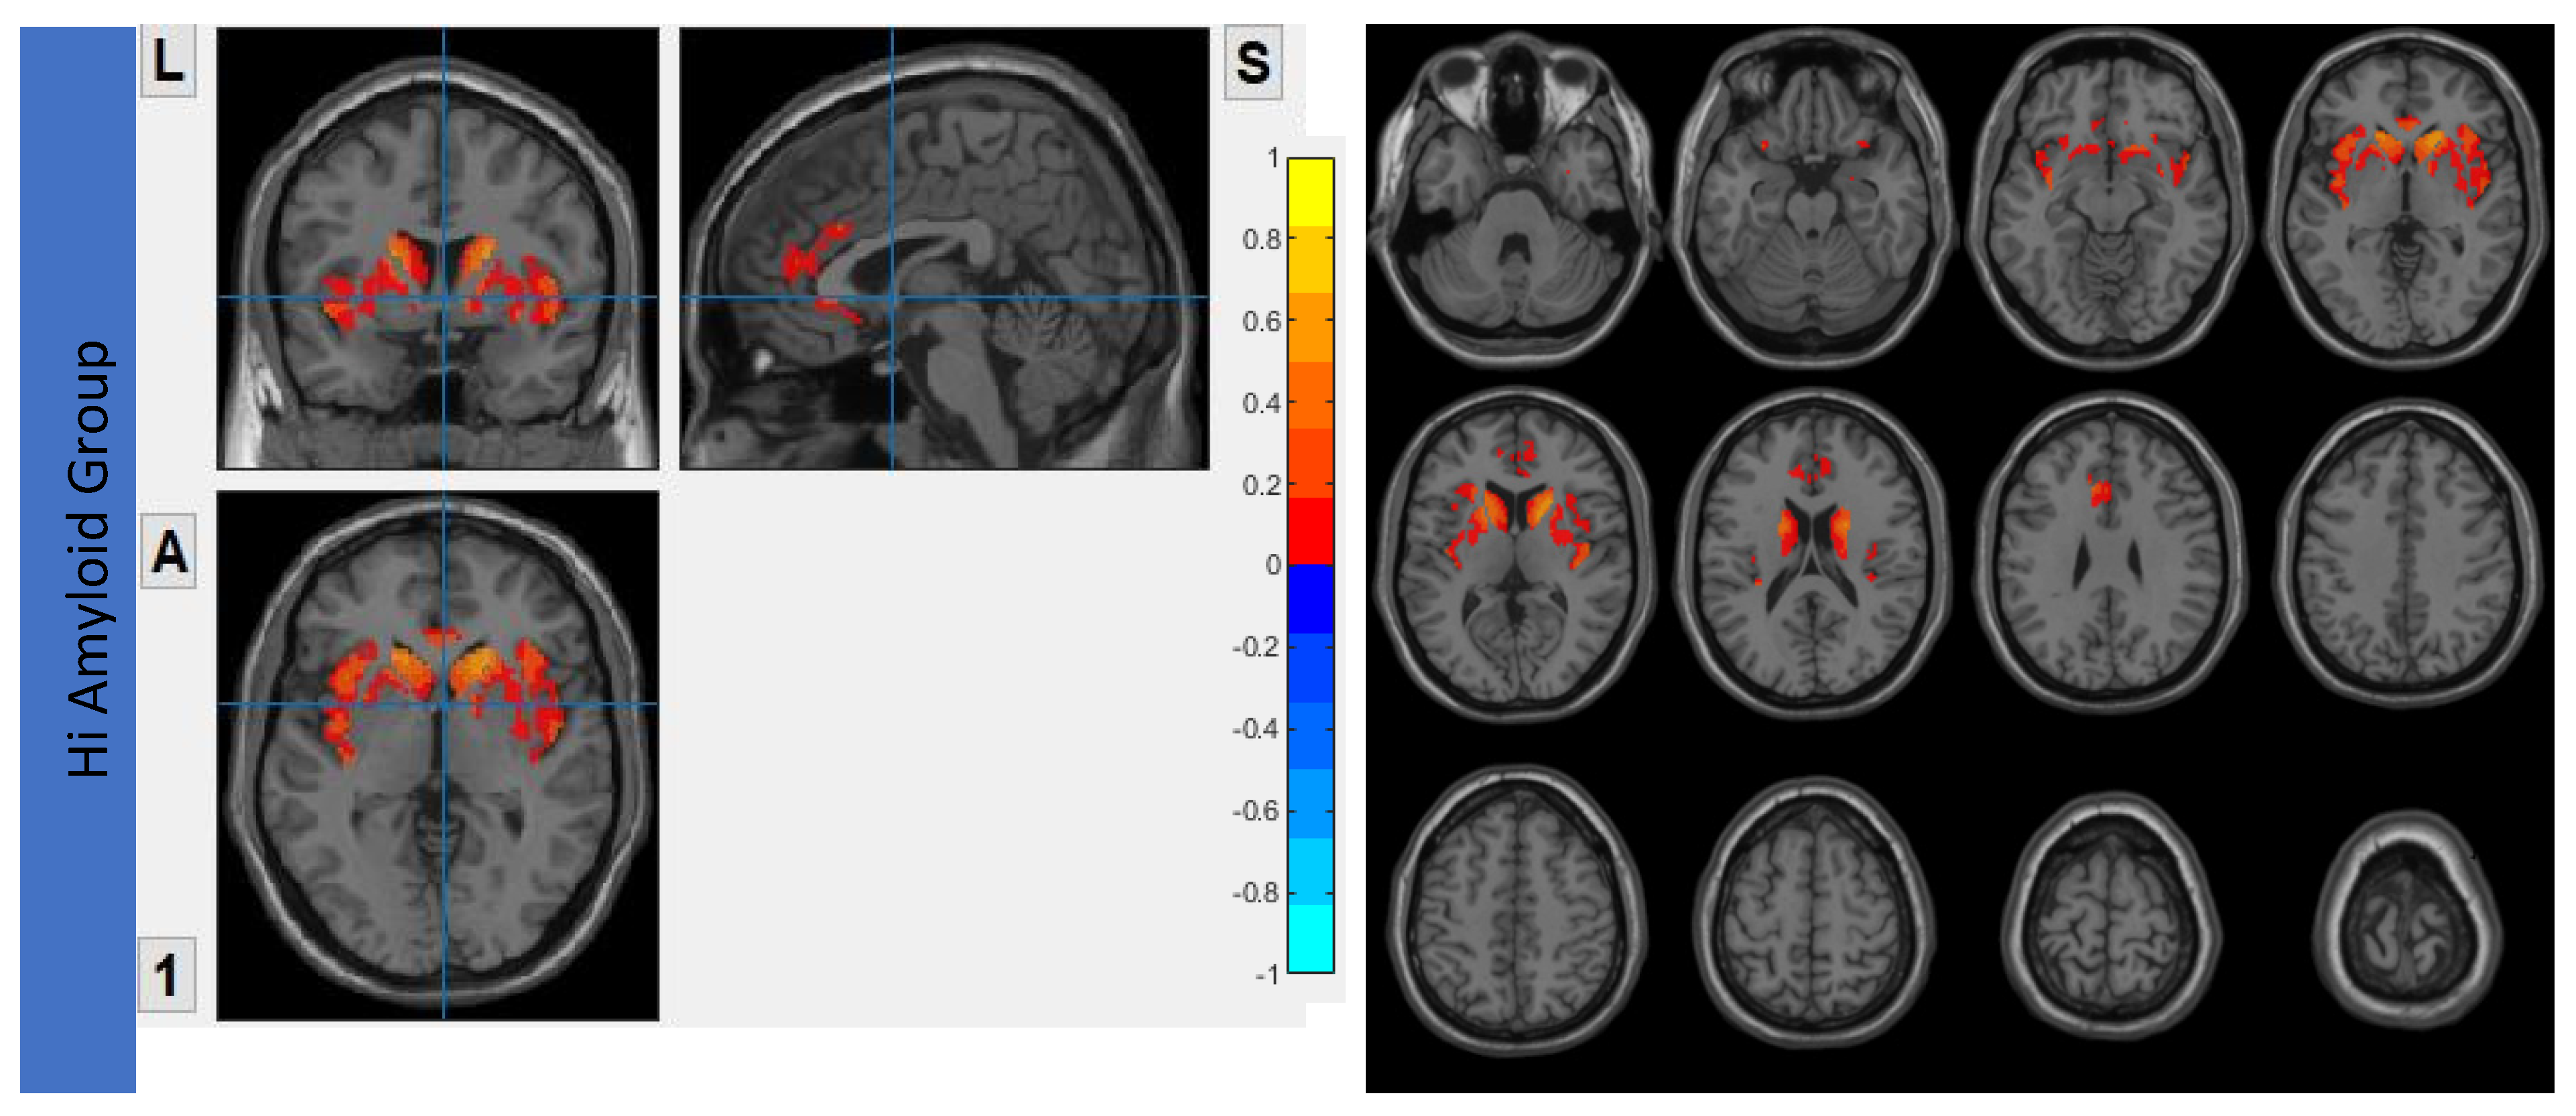

7.4. Within SRN

In the HiAmy group, voxel-wise correlation analysis showed negative correlation (r = −0.257 to −0.536, p < 0.05) in the correlation map, indicating the Aβ accumulation relates to the reduction of functional connectivity of that region. However, in the LowAmy group, voxel-wise correlation analysis showed positive correlation (r = 0.255 to 0.662, p < 0.05) in the correlation map, indicating the Aβ accumulation relates to the increased functional connectivity of that region. Details were shown in Figure 6.

Figure 6.

Correlation between Aβ burden and IFC in SRN.